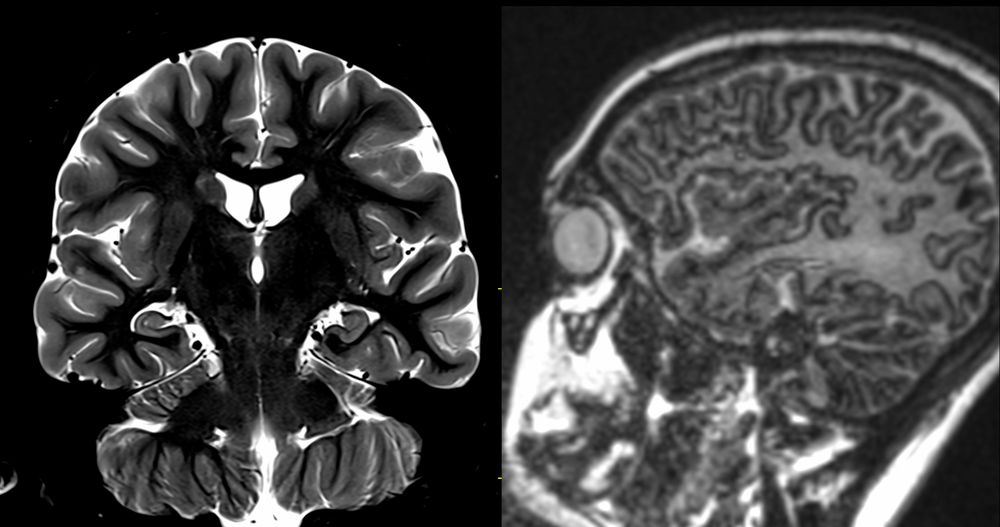

35YF Right cranial neuropathy and headache. #neurology #neurorad #neuroradiology #medicine #radres #radiology #neurosurgery

29 YF with longstanding epilepsy. What do you call this gyral appearance and morphology ? #neurorad #radres #radiology #neuroradiology #neurology #epilepsy